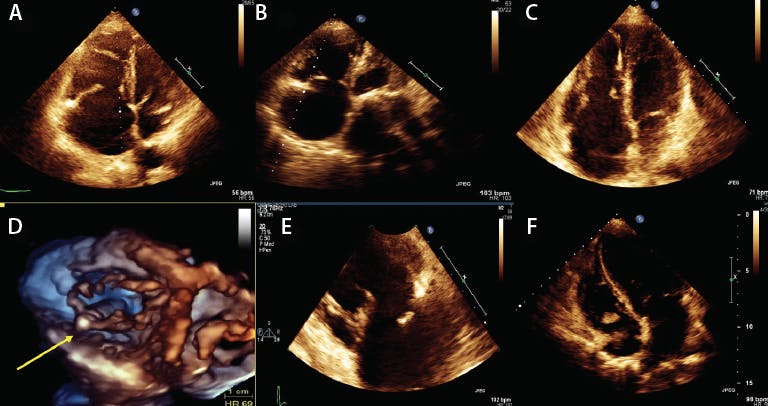

Figure 2. Echo images of carcinoid with thickened septal and anterior leaflets (Carpentier type IIIa) (A); rheumatic TR with doming of septal and anterior leaflets (type IIIa) (B); Ebstein anomaly with apical displacement of septal leaflet (mixed mechanism) (C); pacemaker-induced TR with impinging of posterior leaflet (mixed mechanism) (D); flail TR (type II) (E); endocarditis with large mass on anterior leaflet (mixed mechanism) (F). Note that the mechansim of injury to the leaflets is different for each etiology.

TR can be divided into primary and secondary causes (Table 1; Figure 2Figure 3, and Figure 4). Primary TR is rare and in recent prospective population studies occurs in < 10% of patients.21 Primary TR can be caused by congenital or acquired disease processes that affect the leaflets, chordal structures, or both (Table 1; Figure 2). Common causes for primary TR include rheumatic disease, endocarditis, carcinoid, radiation, drug-induced TR, flail leaflets, or congenital diseases (Figure 2).22 However, recent studies suggest the most common primary causes for TR are related to pacemaker or defibrillator leads.21 These leads can perforate or adhere to leaflets, entangle the chordal apparatus, or impinge leaflets.23 Recently, a three-dimensional echo study has shown that the prevalence of leads impinging on the leaflets in patients with TR (most commonly the posterior or septal) is close to 50%. Although primary TR is rare, it should be recognized and distinguished from secondary TR because it is crucial for patient selection for invasive procedures.24